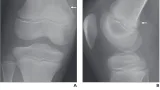

本来は, 造影剤によって白く描出される静脈の中に血栓が黒い陰影が認められます.

造影CTでは骨折側の総腸骨静脈から後脛骨静脈にかけて, 広範囲に血栓が存在.